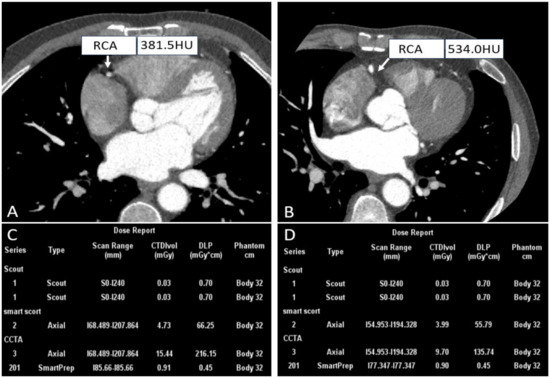

- Wang, X.; Yang, F.; Zhu, Y.; Xiao, Z.; Cui, S. Feasibility Research of Low Concentration Contrast Agent Iodixanol (270 mg I/mL) Combined with the Lower Tube Voltage in Coronary CTA with 640-slice Volumetric CT. J. Hebei North Univ. (Nat. Sci. Ed.) 2018, 83, e92–e99. [Google Scholar]